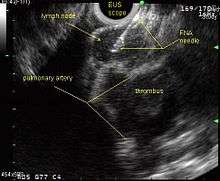

Endobronchial ultrasound (EBUS)

As mentioned in the table, EUS cannot reliably access right sided paratracheal lymph node stations 2R and 4R and may not be optimal for the left sided paratracheal lymph node stations either. An adaptation of the endoscopic ultrasound scope originally designed for the gastrointestinal tract is known as endobronchial ultrasound (EBUS). The instrument is inserted into the trachea rather than the esophagus. There are two types of EBUS bronchoscopes available: radial catheter probe and convex probe EBUS (CP-EBUS),[33] but only the latter concerns us here. Early experience with mediastinal staging by CP-EBUS appears very promising with sensitivities ranging from 92 to 96 percent in 4 series comprising 70 to 502 patients.[34][35][36][37]

Combined ultrasound

Many patients will, if given a choice, prefer an instrument which is inserted into the esophagus (EUS) over one which is inserted into the trachea (EBUS). Furthermore, many patients with suspected lung cancer will have other smoking related illnesses, such as emphysema or COPD, which makes a bronchoscopy-like procedure (EBUS) a higher risk than an upper endoscopy through the esophagus (EUS). An area of active and emerging research concerns the value of combining EUS and EBUS in a single session, one specialist following the other, or -even more convenient- a dual trained operator doing one or the other – or both- as needed.

EUS-FNA and EBUS-FNA are complementary techniques. EUS has the highest yield in the posterior inferior mediastinum, and EBUS is strongest for the superior anterior mediastinum. Some lymph node stations can only be accessed by one method and not the other (for example, station 2 and 4 L and 3 are hard or impossible to see by EUS, stations 5 and 8 cannot be biopsied by EBUS). Together, EBUS and EUS cover the entire mediastinum (except possibly station 6) and complete mediastinal staging should be possible with a combination of these two procedures. This combination could conceptually eliminate the need for most surgical mediastinoscopies and in fact be more comprehensive.

When combined, this approach has been termed “complete medical mediastinoscopy.” EUS-FNA with EBUS may allow near-complete, minimally invasive mediastinal staging in patients with suspected lung cancer [38]